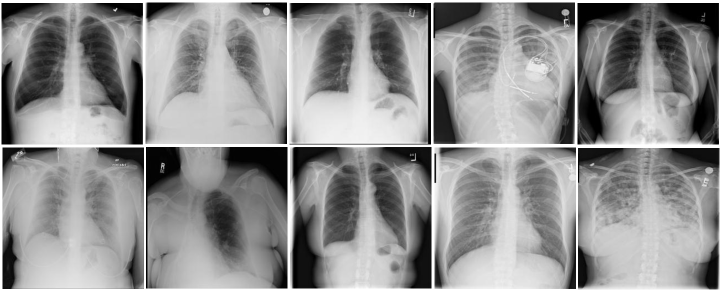

Refer to caption

Figure 3: Dataset Sample